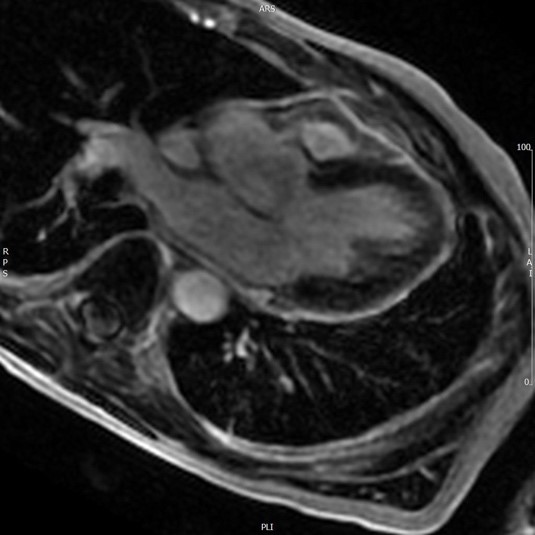

A 52-year old man with a history of diffuse large B cell lymphoma in remission presented with 3 weeks of shortness of breath, cough, fever, and shock. Electrocardiogram revealed sinus tachycardia, diffuse ST segment elevations, PR segment depression, prolonged QTc, and electrical alternans. Bedside echocardiogram was performed, revealing a large circumferential pericardial effusion with tamponade physiology. The patient underwent echo-guided pericardiocentesis with drainage of 400 ml of purulent fluid. Pericardial and blood cultures were positive for Haemophilus influenzae. A CT of the chest was indicative of empyema. Given the patient’s history of rituximab use, autologous stem cell transplant, and profound infection, immunoglobulin levels were drawn and found to be undetectable. The patient received 6 weeks of intravenous antibiotics with IVIG infusions. He was treated with colchicine and aspirin for purulent pericarditis. Two months later, a cardiac MRI was performed, which revealed resolution of the pericardial effusion. No evidence of constrictive pericarditis was noted on MRI, but continued pericardial enhancement was observed. Colchicine was continued for an additional 3 months. The patient made a full recovery at 6 month follow up.